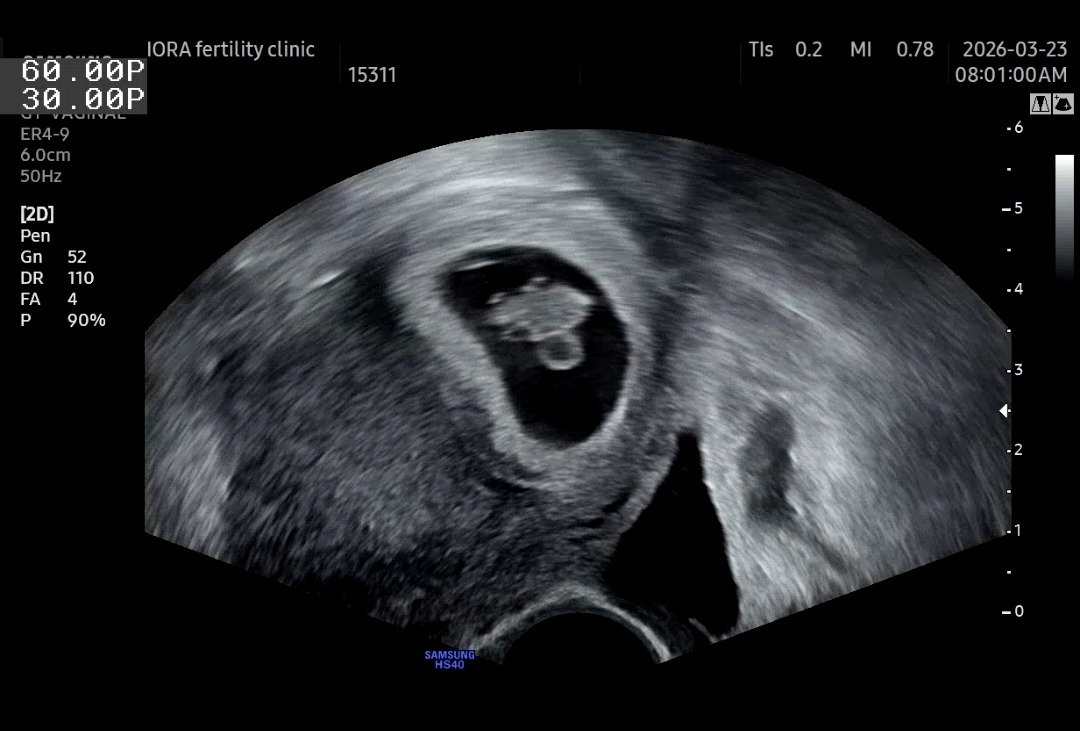

그리고 8주차, 남편이 출장에서 돌아와 처음으로 함께 병원에 갔다.

남편과 처음으로 함께 초음파를 보는데, 아기는 더 자라 있었고,

처음으로 팔다리가 뿅뿅 돋아난 모습이 보였다.

그 모습을 보며 귀여워하고 감탄하고 있던 순간, 선생님의 말이 이어졌다.

KakaoTalk_20260404_230900991.jpg

“심장이 뛰지 않네요.”

지난주에는 분명히 들렸던 심장 소리가 이번에는 들리지 않았다.

심장 부근에서 보여야 할 혈류도 보이지 않았다.

내 몸에서는 여전히 아기에게 피를 보내고 있었지만, 아기의 심장은 멎어 있었다.